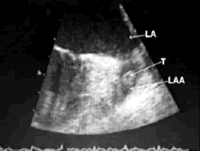

本病例应选择阿司匹林还是华法林治疗呢?该患者仅有一项高血压符合华法林或阿司匹林治疗适应证,但是入院后超声心动图检查发现其左心房内有云雾状改变,进一步经食管超声证实其左心耳内可见不活动的低回声团块(图1),提示左心耳内血栓形成。此时必须口服华法林进行抗凝治疗并监测INR,同时应该对患者进行心脏超声随访。

图1 经食管超声心动图 左心耳(LAA)内血栓形成